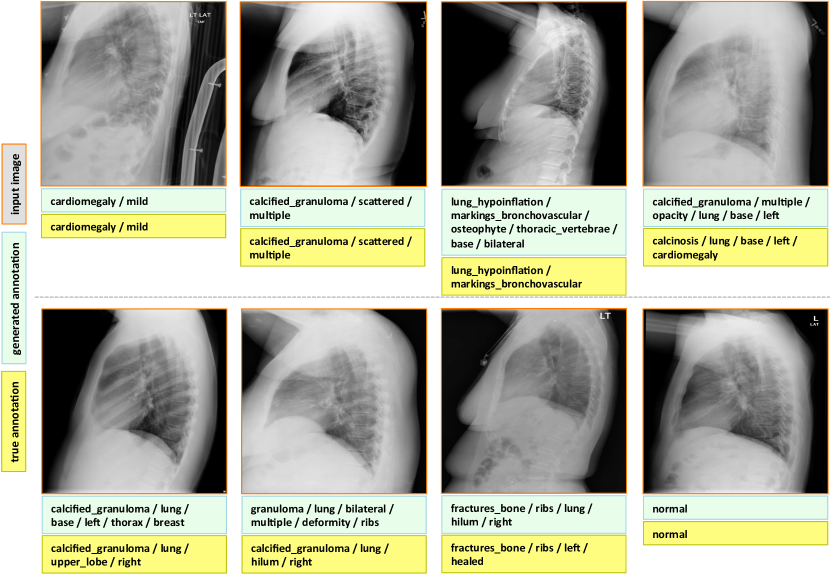

Appendix C More Annotation Generation Examples

More annotation generation examples are provided in Figures 10 and 11. Overall, the system generates promising results on predicting disease (labels) and its context (attributes) in the images. However, rare disease cases are more difficult to detect. For example, the cases pulmonary_atelectasis, spondylosis, and density (Figure 10), as well as foreign_bodies, atherosclerosis, costophrenic_angle, deformity (Figure 11) are much rarer in the data than calcified_granuloma, cardiomegaly, and all the frequent cases listed in Table 1 of the main paper.

Furthermore, the (left or right) location of the disease cannot be identified in a lateral view (obtained by scanning the patient from the side), as shown in Figure 11. Since our dataset contains a limited number of disease cases, we treat each x-ray image and report as a sample, and do not account for different views.

For future work, we plan to improve prediction accuracy by both (a) accounting for the different views, and (b) collecting a larger dataset to better account for rare diseases.